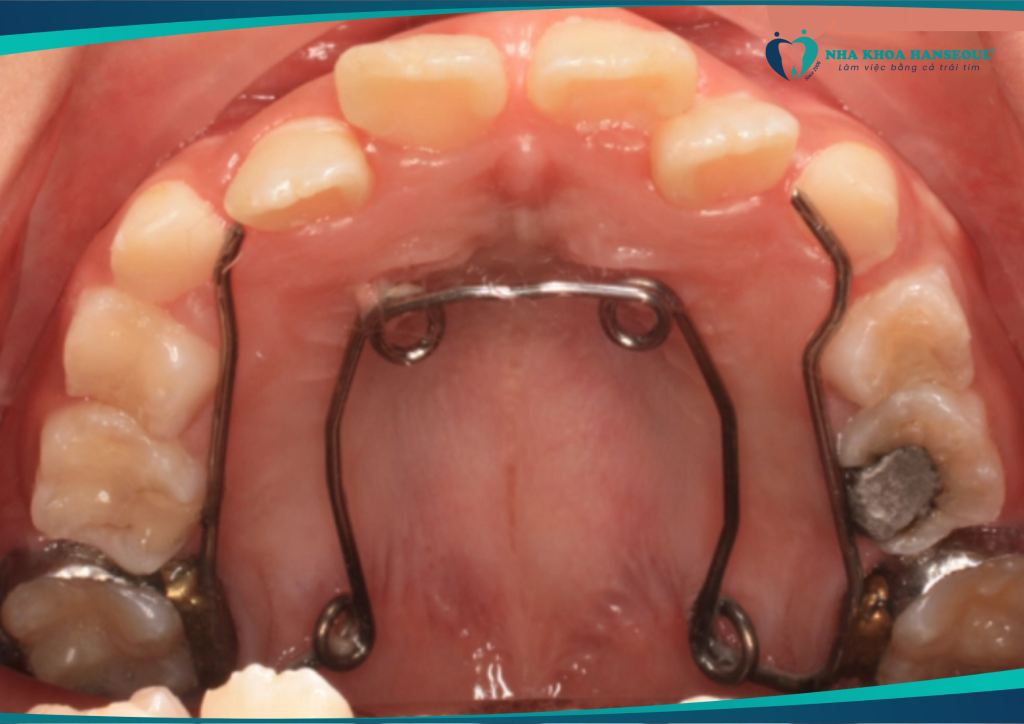

- Sử dụng khí cụ hỗ trợ hiện đại: Các khí cụ như nong hàm, mini vít có thể tạo thêm khoảng trống thay cho việc nhổ răng.